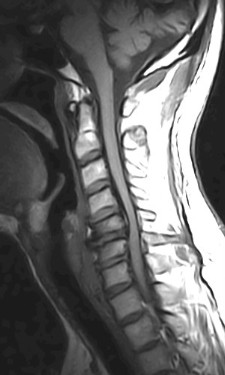

October 2005 - Ossification of the Posterior Longitudinal Ligament (OPLL)

There is evidence of a markedly thickened/ossified posterior longitudinal ligament over the C3 to the C7 vertebral levels with resultant canal stenosis and cord compression. The cord shows a hyperintense signal on the T2W images and is also decreased in caliber (edema/ischemia/gliosis - myelomalacia).

OPLL may be classified into four types on the sagittal MR images.

• Continuous - extending over several vertebral bodies.

• Segmental - multiple separate retrovertebral lesions

• Mixed - a combination of continuous and segmental

• Circumscribed - confined to the retrodiscal space

Continuous type is usually thicker, may contain bone marrow and is most frequently associated with severe cord compression. Detection is dependent upon the morphology of the process, presence or absence of bone marrow or calcium in the ligament or by it's effect upon the ventral subarachnoid space, dura and spinal cord. Hyperintense signal on the T1W images may represent fatty marrow. The hypertrophied ligament is hypointense. Intense enhancement within the ligament may be seen. T2W images help to assess the cord (myelopathy - due to direct compression on the spinal cord and anterior spinal artery).